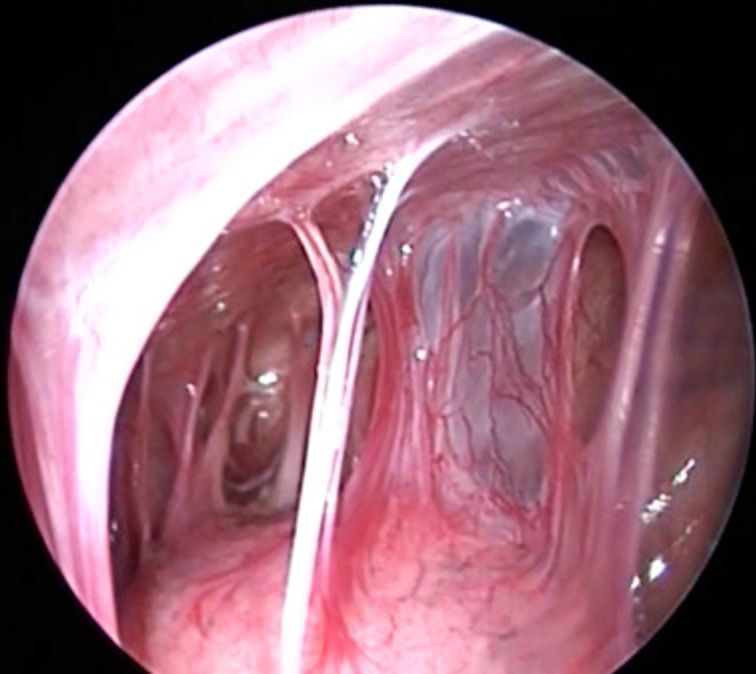

14/Imaging of trapped lung will typically show pleural thickening and loculation. An air contrasted CT can be used to better visualize the visceral pleura rind or you can use direct visualization with video-assisted thoracoscopy. @ReenaHem @ERitterMD @VCURadRes @MarkZieglerMD

16/ Management of an asymptomatic trapped lung is NOT pleural drainage as the effusion will just re-accumulate. However, decortication of the visceral pleura rind with VATS is typically your treatment for symptomatic patients who are surgical candidates. @VCUIMClerkship